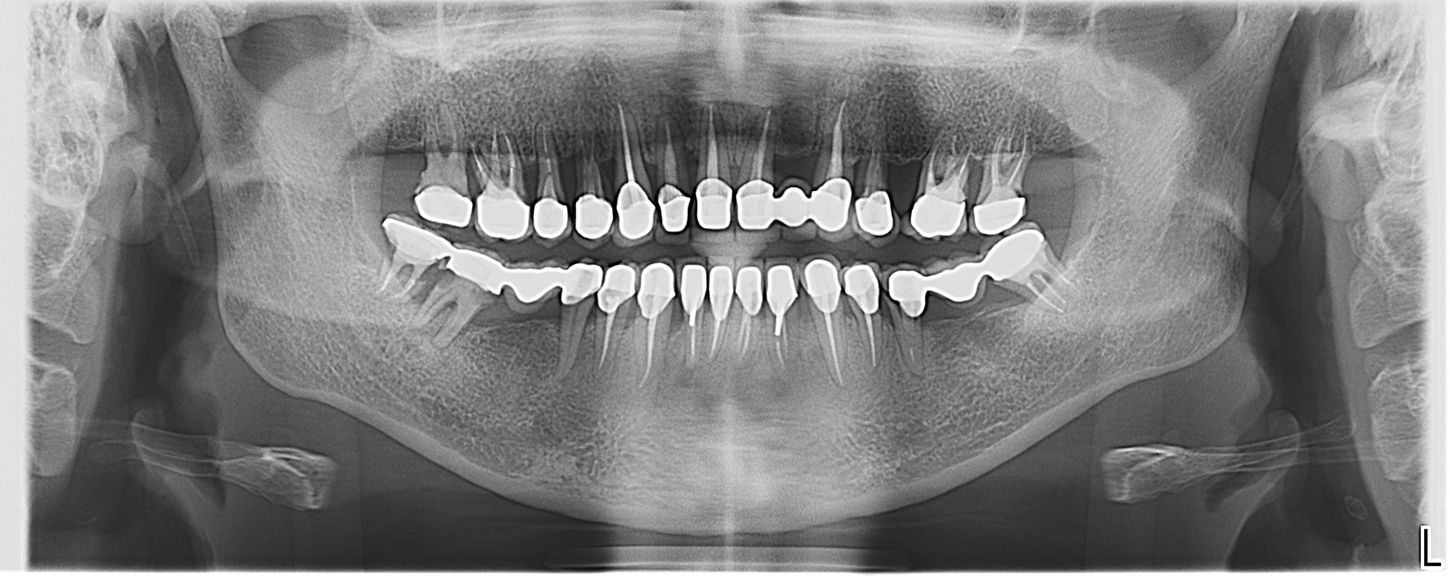

В процессе сбора семейного анамнеза выяснено, что родители пациентки страдали хроническим пародонтитом. Пациентка выросла на крайнем севере России, где был ограниченный пищевой рацион (из-за труднодоступности местности) и очень плохой состав воды, в первую очередь - недостаточное содержание фтора. Еще из факторов риска – курение; нерациональное протезирование и, как следствие, неравномерное распределение жевательной нагрузки; снижение высоты прикуса; наличие большого количества поднутрений, нависающих краёв реставраций, гиперконтуров, недостаточная точность прилегания коронок; неудовлетворительная гигиена полости рта. Десны воспаленные, отечные, имелись пародонтальные карманы разной степени выраженности у всех зубов. КЛКТ выявила тяжелую степень атрофии костной ткани, дефекты костной ткани в области фуркаций, расширение пространства периодонтальной связки у множества зубов. (Илл. 5)

Иллюстрация 5